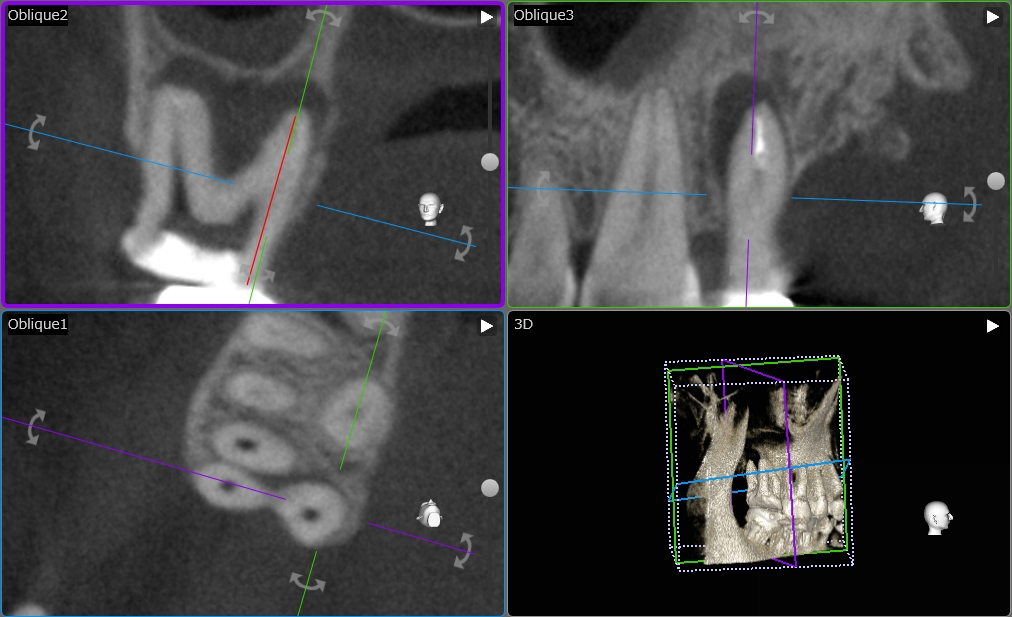

術前の状態です。

歯の根っこの周りが黒くなっており、骨が炎症を起こしていることがわかります。

今回は根管内の消毒に4回、MTAセメントという成績のいい材料を使用して根管内を封鎖、経過観察に3ヶ月以上を置きました。

先ほどのレントゲン像とは違い、根の周りの黒い像が消えているのがお分かりいただけるかと思います。